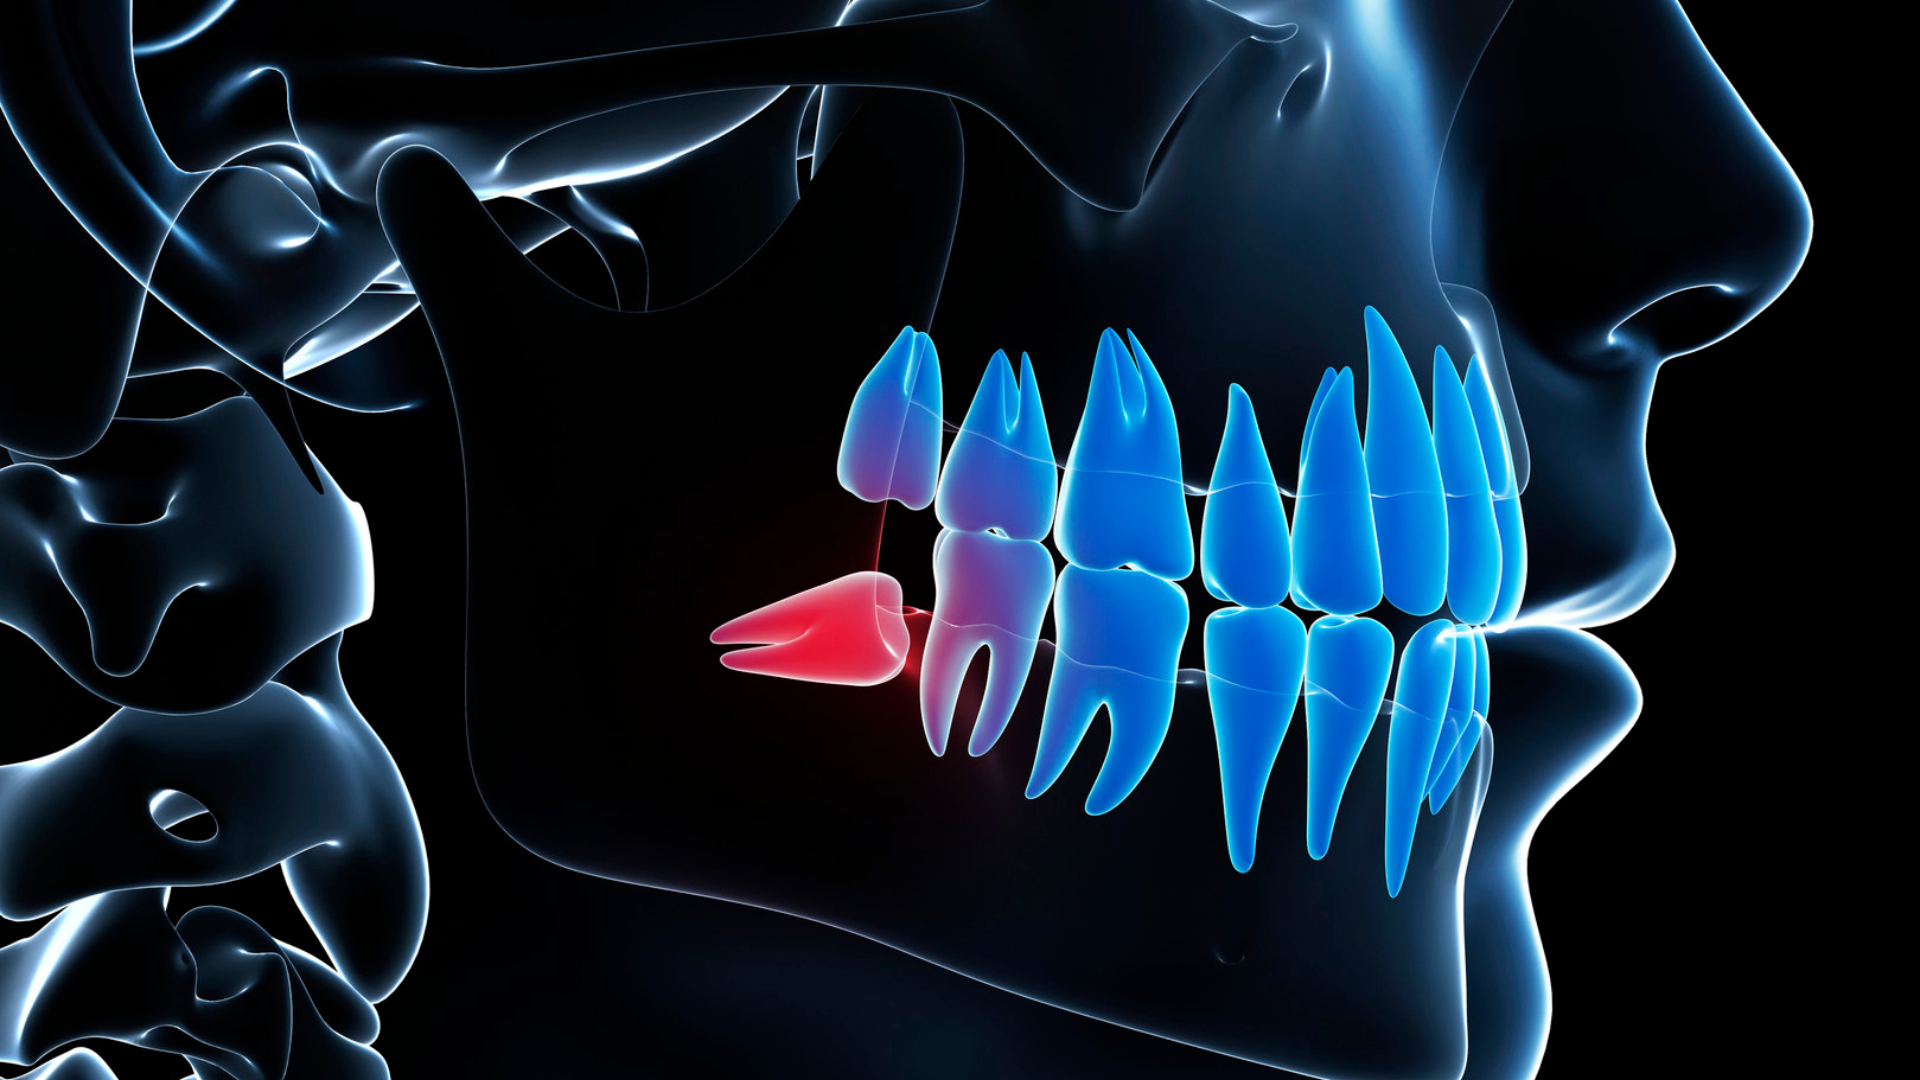

Răng khôn mọc lệch ngang là tình trạng thân răng nằm ngang, đâm vào răng số 7 hoặc xương hàm. Điều này khiến răng bị kẹt hoàn toàn hoặc một phần dưới nướu.

Các bất thường này khiến răng khôn không thể mọc thẳng nên nằm ngang và gây đau hoặc chèn ép sang răng bên cạnh.

- Sâu răng số 7 do bề mặt tiếp xúc khó vệ sinh.

- Viêm quanh thân răng với triệu chứng sưng nướu và đau kéo dài.

- Mất xương ổ răng, tiêu xương vùng phía sau hàm.